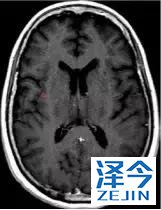

脑转移病变显示缩小了95%!

初始, 2018年6月 3周期 2018年8月